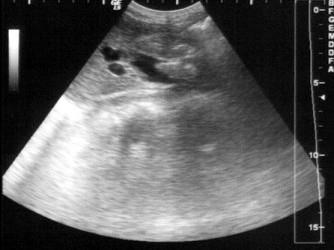

问题 患者女32岁,反复上腹部疼痛10年余,加重时皮肤、巩膜黄染。B超检查如图所示,根据超声声像图,诊断为?(?)

选项 A.胆总管蛔虫 B.胆总管癌 C.胆总管结石 D.胆总管内胆泥淤积 E.胆总管内引流管回声

答案 C